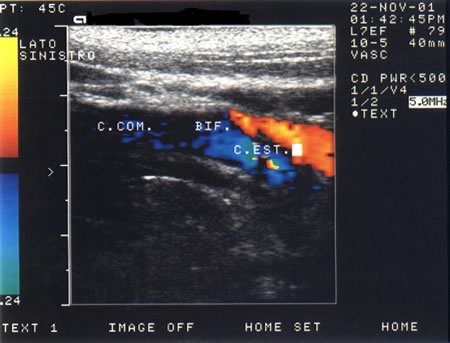

La ripetizione della TAC (Fig. 1) dopo alcuni giorni ha messo in evidenza alcune aree ipodense a sx, a livello parietale e temporo-mandibolare, che non presentano enhancement dopo mezzo di contrasto, dato che esclude un tumore o un ascesso. Finalmente esegue angio-RMN (Fig. 2) che mostra una occlusione della carotide interna in un quadro suggestivo di dissezione della carotide interna. A quel punto viene rivalutata la storia e ripete l'eco-doppler dei vasi del collo (Fig. 3 e Fig. 4) che mostra un ostruzione della carotide interna di sinistra ad 1 cm dalla biforcazione, senza alterazioni a destra. Il recupero del bambino è stato quasi completo.

Eco-doppler della carotide sinistra: ostruzione ad 1cm dalla biforcazione